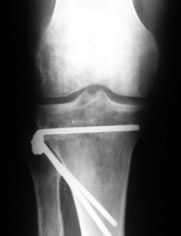

AC> Вот, с учетом и без учета, и на разных уровнях...

AC> Саша Артемьев, может, для данного случая свой вариант нарисуешь?

Из приведнной схемы не совсеим понял что означают разноцветные линии.

И зачем латерализация периферического фрагмента. Я всегда делаю медиализацию. См схему. И для данного случая медиализация подходит как нельзя лучше.

a> Из приведнной схемы не совсеим понял что означают разноцветные линии.

Черные - это нынешняя механическая ось. Красные - это планируемая правильная ось.

a> И зачем латерализация периферического фрагмента.

;-) Читайте Палея. Стр. 114-115.

a> Я всегда делаю медиализацию. См схему. И для данного случая

Медиализация - это чисто эстетический прием, как я понимаю. Поскольку если делать остеотомию ниже вершины деформации, для восстановления оси надо делать смещение по ширине, в данном случае как раз латерализацию.

А вот на схемке без осей - там на разных уровнях (который правильнее?) устранение варуса чисто открытым клином без медиализации-латерализации. Если как-то так сделать - этого недостаточно будет?

Картинки - в приложении.Будут вопросы - готов ответить.

Ещё картинка - схема. Хотя у Соломина всё написано.